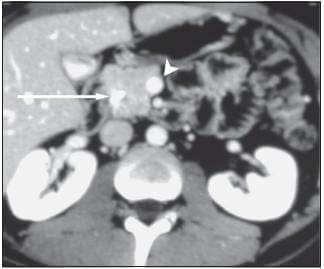

Este tumor tiene un mal pronóstico no sólo por su agresividad sino porque se diagnostica en estadios avanzados debido a su ubicación retroperitoneal, que no está al alcance de la mayoría de los exámenes diagnósticos. Para intentar mejorar su detección temprana se inventó hace más de 20 años la ecoendoscopia, ya que permite colocar el transductor ecográfico más cerca de este órgano y hacer la evaluación de toda clase de tumores pancreáticos (36). La TC abdominal (figura 15) posee también precisión diagnóstica en la evaluación del paciente con sospecha de tumor pancreático, con sensibilidad y especificidad de 83% y 93%, respectivamente, y presenta evidentes ventajas en la estadificación de la lesión (37). No obstante, la ecoendoscopia (figura 16) tiene un rendimiento diagnóstico superior al de la TC, con sensibilidad y especificidad de 94% y 100%, respectivamente (38). Es así como la ecoendoscopia se ha convertido en el examen de elección para la evaluación de pacientes en quienes se sospecha una masa o lesión del páncreas. En nuestra práctica clínica, con la ecoendoscopia hemos encontrado muchas masas de la cabeza del páncreas que no fueron detectadas por la TC, incluso con tomógrafos modernos como los que utilizan técnica helicoidal.

FIGURA 15. La flecha larga señala la masa ubicada en la cabeza del páncreas y la flecha corta señala que los vasos están respetados por la lesión.

FIGURA 16. En el centro de la imagen se observa una masa heterogénea ubicada en la cabeza del páncreas, la cual invade al colédoco distal y a la porta que esta detrás de él.